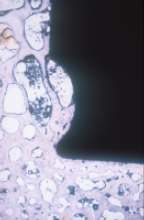

Abb. 13

Oberfläche eines explantierten Titanschaftes (Ti) mit darauf angewachsenem, neu gebildetem Knochengewebe (B)

Bleibt diese Osseointegration über Jahre bestehen? Die folgenden Bilder illustrieren dies. Abb. 15a und b zeigen das Präparatröntgen einer 83-jährigen Patientin, welche 20,7 Jahre nach Implantation des Titaniumschaftes verstorben ist. Es finden sich stabile Verhältnisse. Die Abbildungen c und d zeigen, dass das Implantat (Ti) stabil im umgebenden Knochen verankert ist (Dünnschliffpräparate Prof. Dr. F. Lintner, Pathologie, Otto-Wagner-Spital). Dies bedeutet, dass die Osseointegration auch beim alten und sehr alten Menschen funktioniert.

Abb. 15c